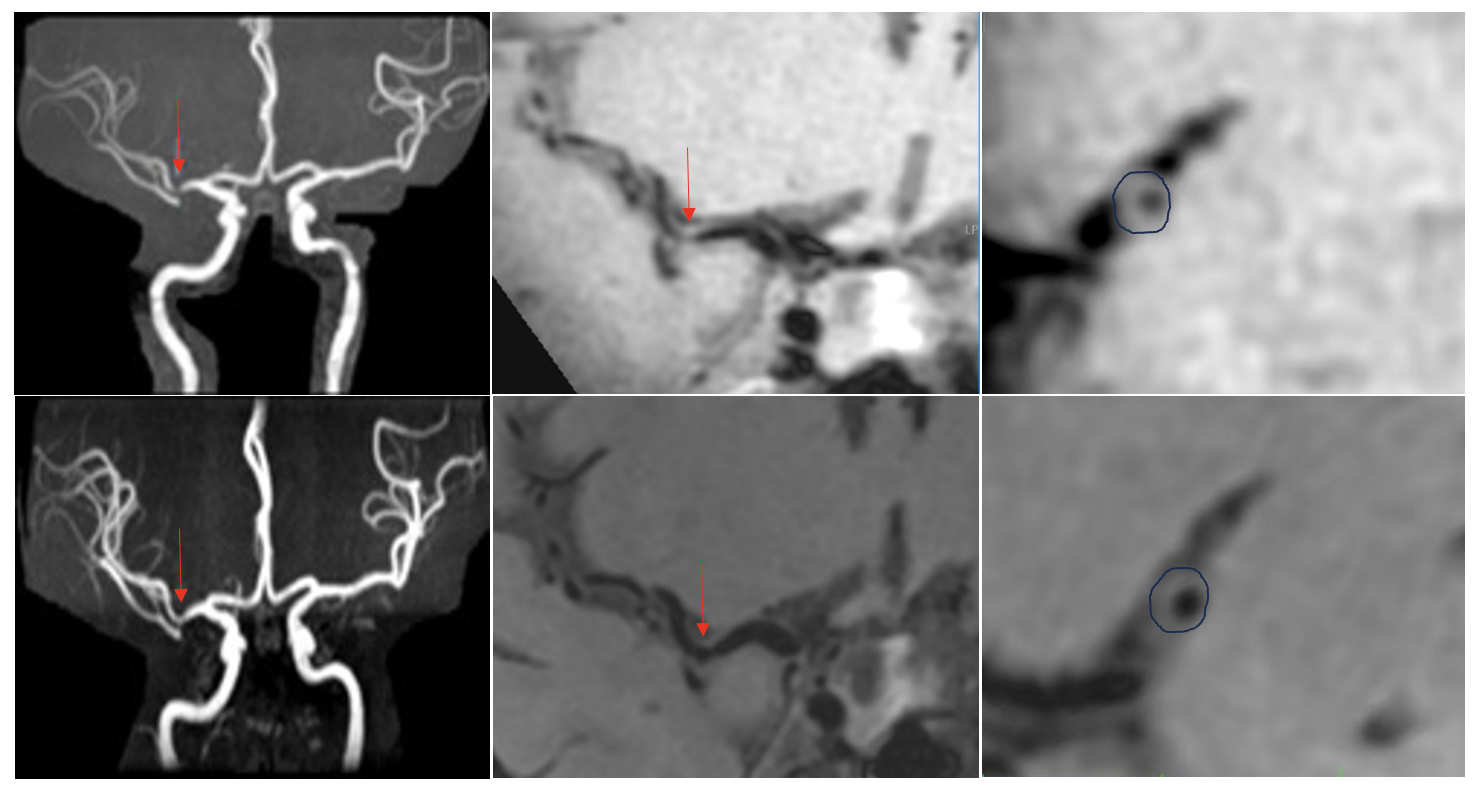

Abstract Body: Background and Purpose: We aimed to investigate the effects of evolocumab, a proprotein convertase subtilisin/kexin type-9 inhibitor for intensive lipid-lowering, on intracranial atherosclerotic stenosis (ICAS).

Methods: From a prospectively established high-resolution magnetic resonance imaging (HR-MRI) database, consecutive ICAS (>50%) patients with two detections of HR-MRI over six months were included in this study. The patients were divided into two groups: those with (evolucomab+) or without (evolocumab-) evolocumab add-on therapy. The primary outcomes were the percentage change in plaque burden and plaque response (plaque regression >5%) rate. The second outcome was the percentage change in stenosis degree. Cox regression analysis was used to estimate the association between evolocumab add-on therapy and the above outcomes in both general and subgroup (intensive statin vs. non-intensive statin) analysis.

Conclusions: Evolocumab add-on therapy over six months is superior to statin alone in reversing symptomatic ICAS.